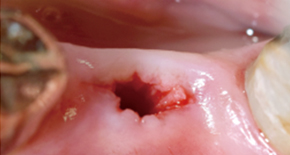

2. Forming minimal implant hole

3. Placing MagiCore